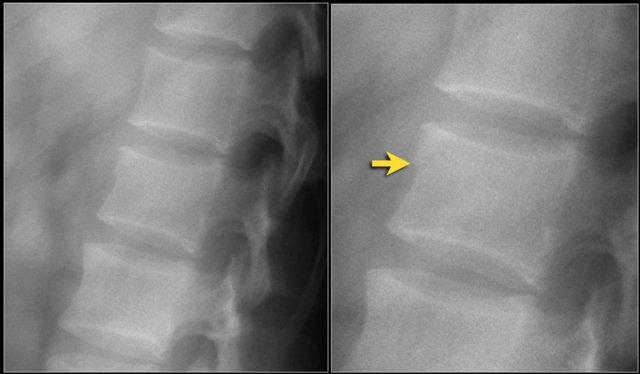

Các hình ảnh cho thấy một trường hợp gãy xương nén.

Dấu hiệu duy nhất quan sát được là sự gián đoạn vỏ xương ở thành trước trên của thân đốt sống và mất chiều cao nhẹ ở phía trước.

Vỏ xương phía sau thân đốt sống còn nguyên vẹn.

Hình tái tạo mặt phẳng đứng dọc cũng cho thấy sự gián đoạn vỏ xương.

Lưu ý rằng trên lát cắt axial dày 2,5mm, có thể bỏ sót các gãy xương này.

Cần xem xét các lát cắt mỏng để phát hiện những gãy xương tinh tế như vậy.